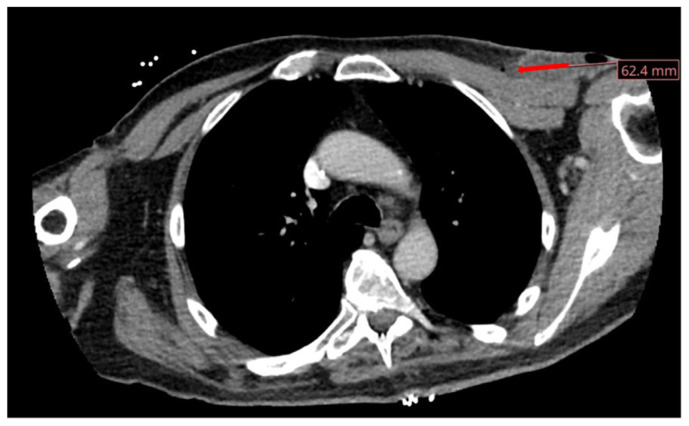

Implantable cardiac devices, including cardiac pacemakers, are not without risk for infection, carrying a mortality and morbidity of around 5-15%. Gram positive organisms are most common in 91% of cases, whereas gram negative organisms are less common, found in 2% of cases secondary to gram negative organisms other than Pseudomonas aeruginosa. Here, we present a rare case of the gram-negative organism Proteus mirabilis leading to a pacemaker site infection.